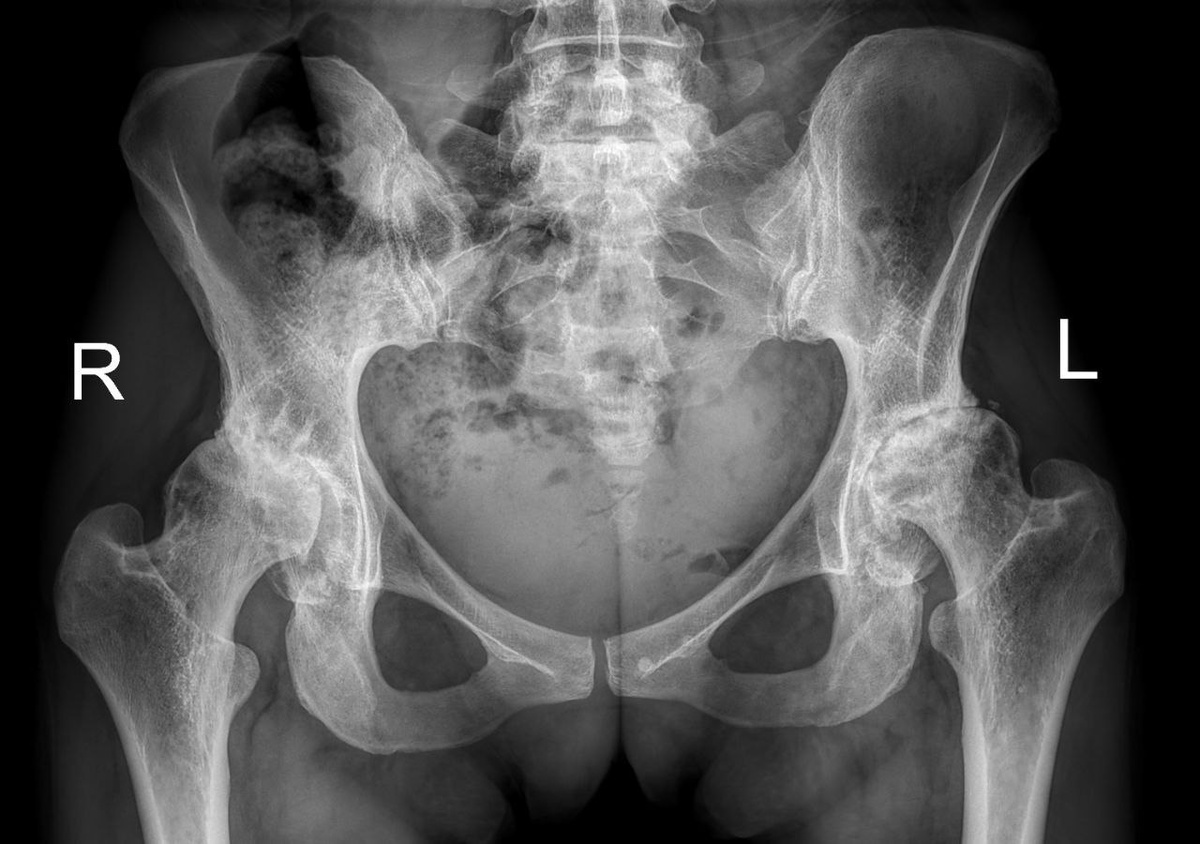

Снимок до операции

Основанием для операции стал вторичный коксартроз III стадии, отягощённый атрофией мышц и контрактурами суставов.